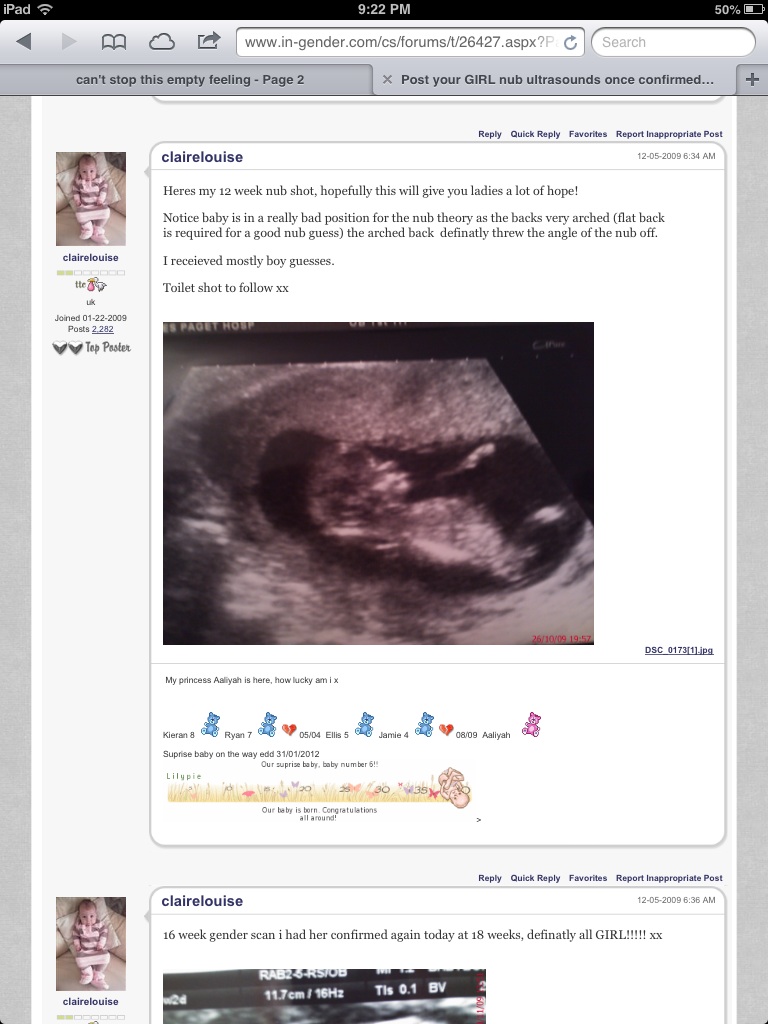

This is my ultrasound 11weeks6days. Is there a clear nub? Any guesses?thank you so much!